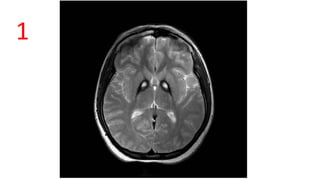

EYE OF TIGER APPEARANCE

Hallervorden-Spatz disease

T2 Hyperintense in Gp surrounded by hypointense

gliosis and neuronal loss excessive iron accumulation